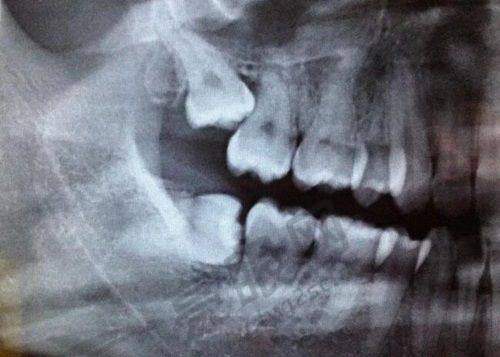

设备情况

门诊部配备了一些数字化设备,如CBCT机和根管治疗仪等。这些设备有助于确保诊疗体验的效率高率,让患者能在更短的时间内完成诊断和治疗。